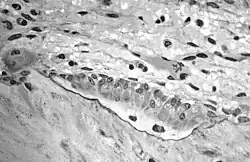

Aufnahme mehrerer Osteoblasten, den knochenaufbauenden Gegenspielern der Osteoklasten. In der TEM-Aufnahme ist das von den Osteoblasten synthetisierte Osteoid als helle, zur mineralisierten Knochenmatrix hin scharf abgegrenzten Zone (schwarze Grenzlinie) mit zwei eingelagerten Osteozyten (ehemalige Osteoblasten) gut zu erkennen.